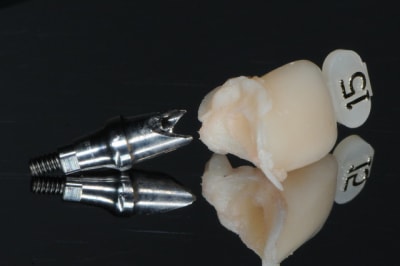

1-2: l'ensemble prothétique; pilier-vis-couronne

3: j+3mois1/2

photo final: j+1 an

voilà merci pour vos commentaires.